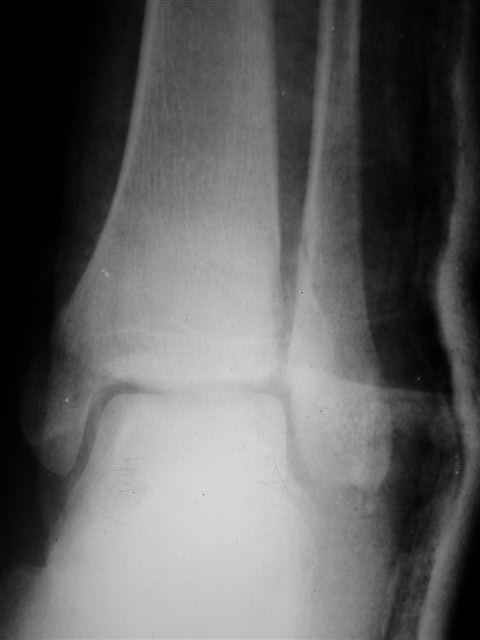

В первом письме я упомянул о закрытом повреждении правого голеностопного сустава, эверсионно-пронационный механизм травмы - перелом внутренней лодыжки( поперечный, на уровне суставной щели) и отрывной перелом бугорка Chaput. После обработки открытых переломов бедра и большеберцовой кости в эту же сессию перелом внутренней лодыжки фиксировал двумя расходящимися спицами, бугорок Chaput двумя тягловыми винтами 3,5 мм. Раны заживают благополучно. Учитывая повреждение наружной группы мышц, активное разгибание в голеностопном суставе ограничено. Пассивная + пассивно-активная мобилизация голеностопного сустава с физиотерапевтом.